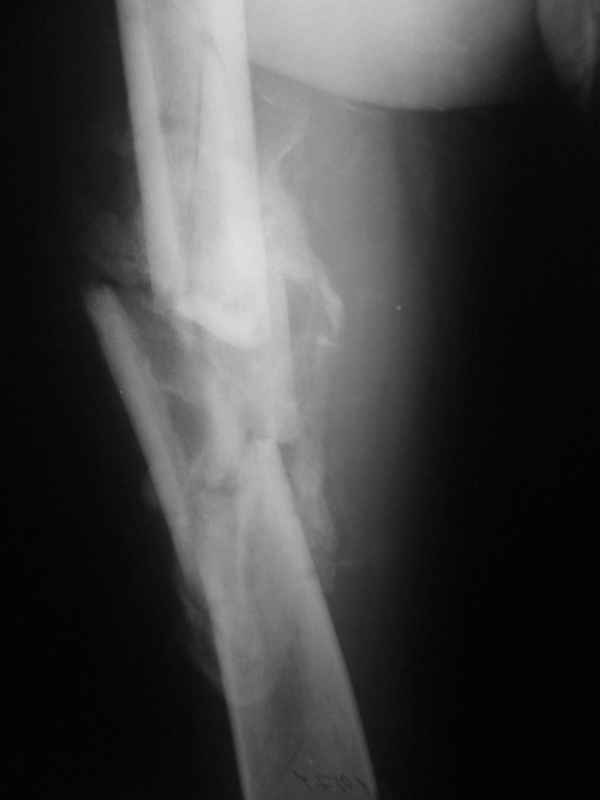

Re: Неправильно срастающийся оскольчатый перелом бедра